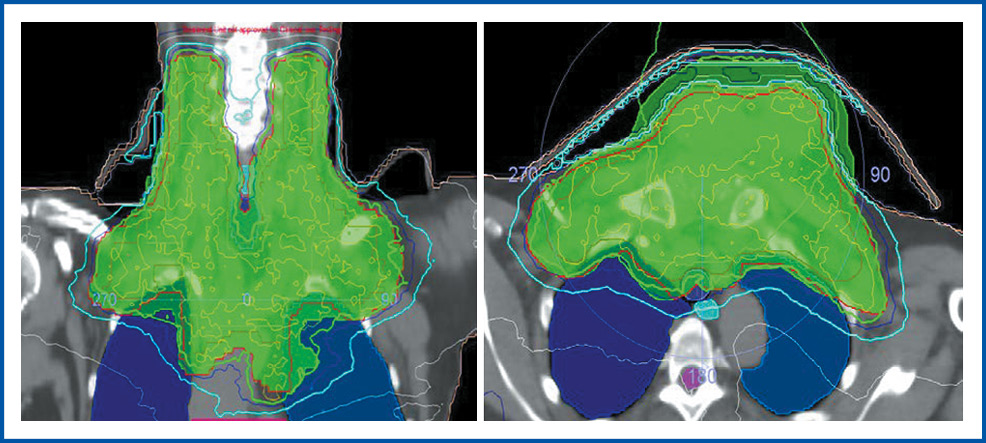

В отдел лучевой терапии МНИОИ им. П.А. Герцена – филиала ФГБУ «НМИЦ радиологии» с 14 по 20 июня 2022 г. по витальным показаниям проведен курс конформной дистанционной ЛТ на ускорителе электронов Elektra Infinity. В область gross tumor volume (GTV) вошли все определяемые опухолевые очаги по данным ПЭТ-КТ: узел передней грудной стенки в области грудины с мягкотканым компонентом, рукоятка и тело грудины, клетчатка переднего средостения, паратрахеальный лимфатический узел справа; конгломерат парааортальных лимфатических узлов на уровне дуги аорты, лимфатические узлы шеи, надподключичной области с обеих сторон, clinical tumor volume (СTV): GTV + 10 мм. Planned tumor volume (PTV) сформирована с отступом краниокаудально 12 мм, 10 мм в остальных направлениях от CTV. РОД – 6 Гр 5 раз в неделю, СОД – 30 Гр. Биологическая эквивалентная доза (EDQ2), рассчитываемая на основе LQ-модели, в данном случае составила 54 иГр при α/β=3.

На рис. 3 отражено дозное распределение в облучаемом объеме.

Рис. 3. Дозное распределение в объеме облучения (в процентах указана 95 и 80% изодозная кривая).

Fig. 3. Dose distribution in the irradiation volume (95% and 80% of the isodose curve are indicated in percentage).

Получено хорошее дозное покрытие:

- GTV – 100% доза покрывает 100% объема;

- CTV – 95% доза покрывает 95% объема;

- PTV – 95% доза покрывает 95% объема.

Толерантные дозы на критические органы не превышают допустимых по QUANTEC.